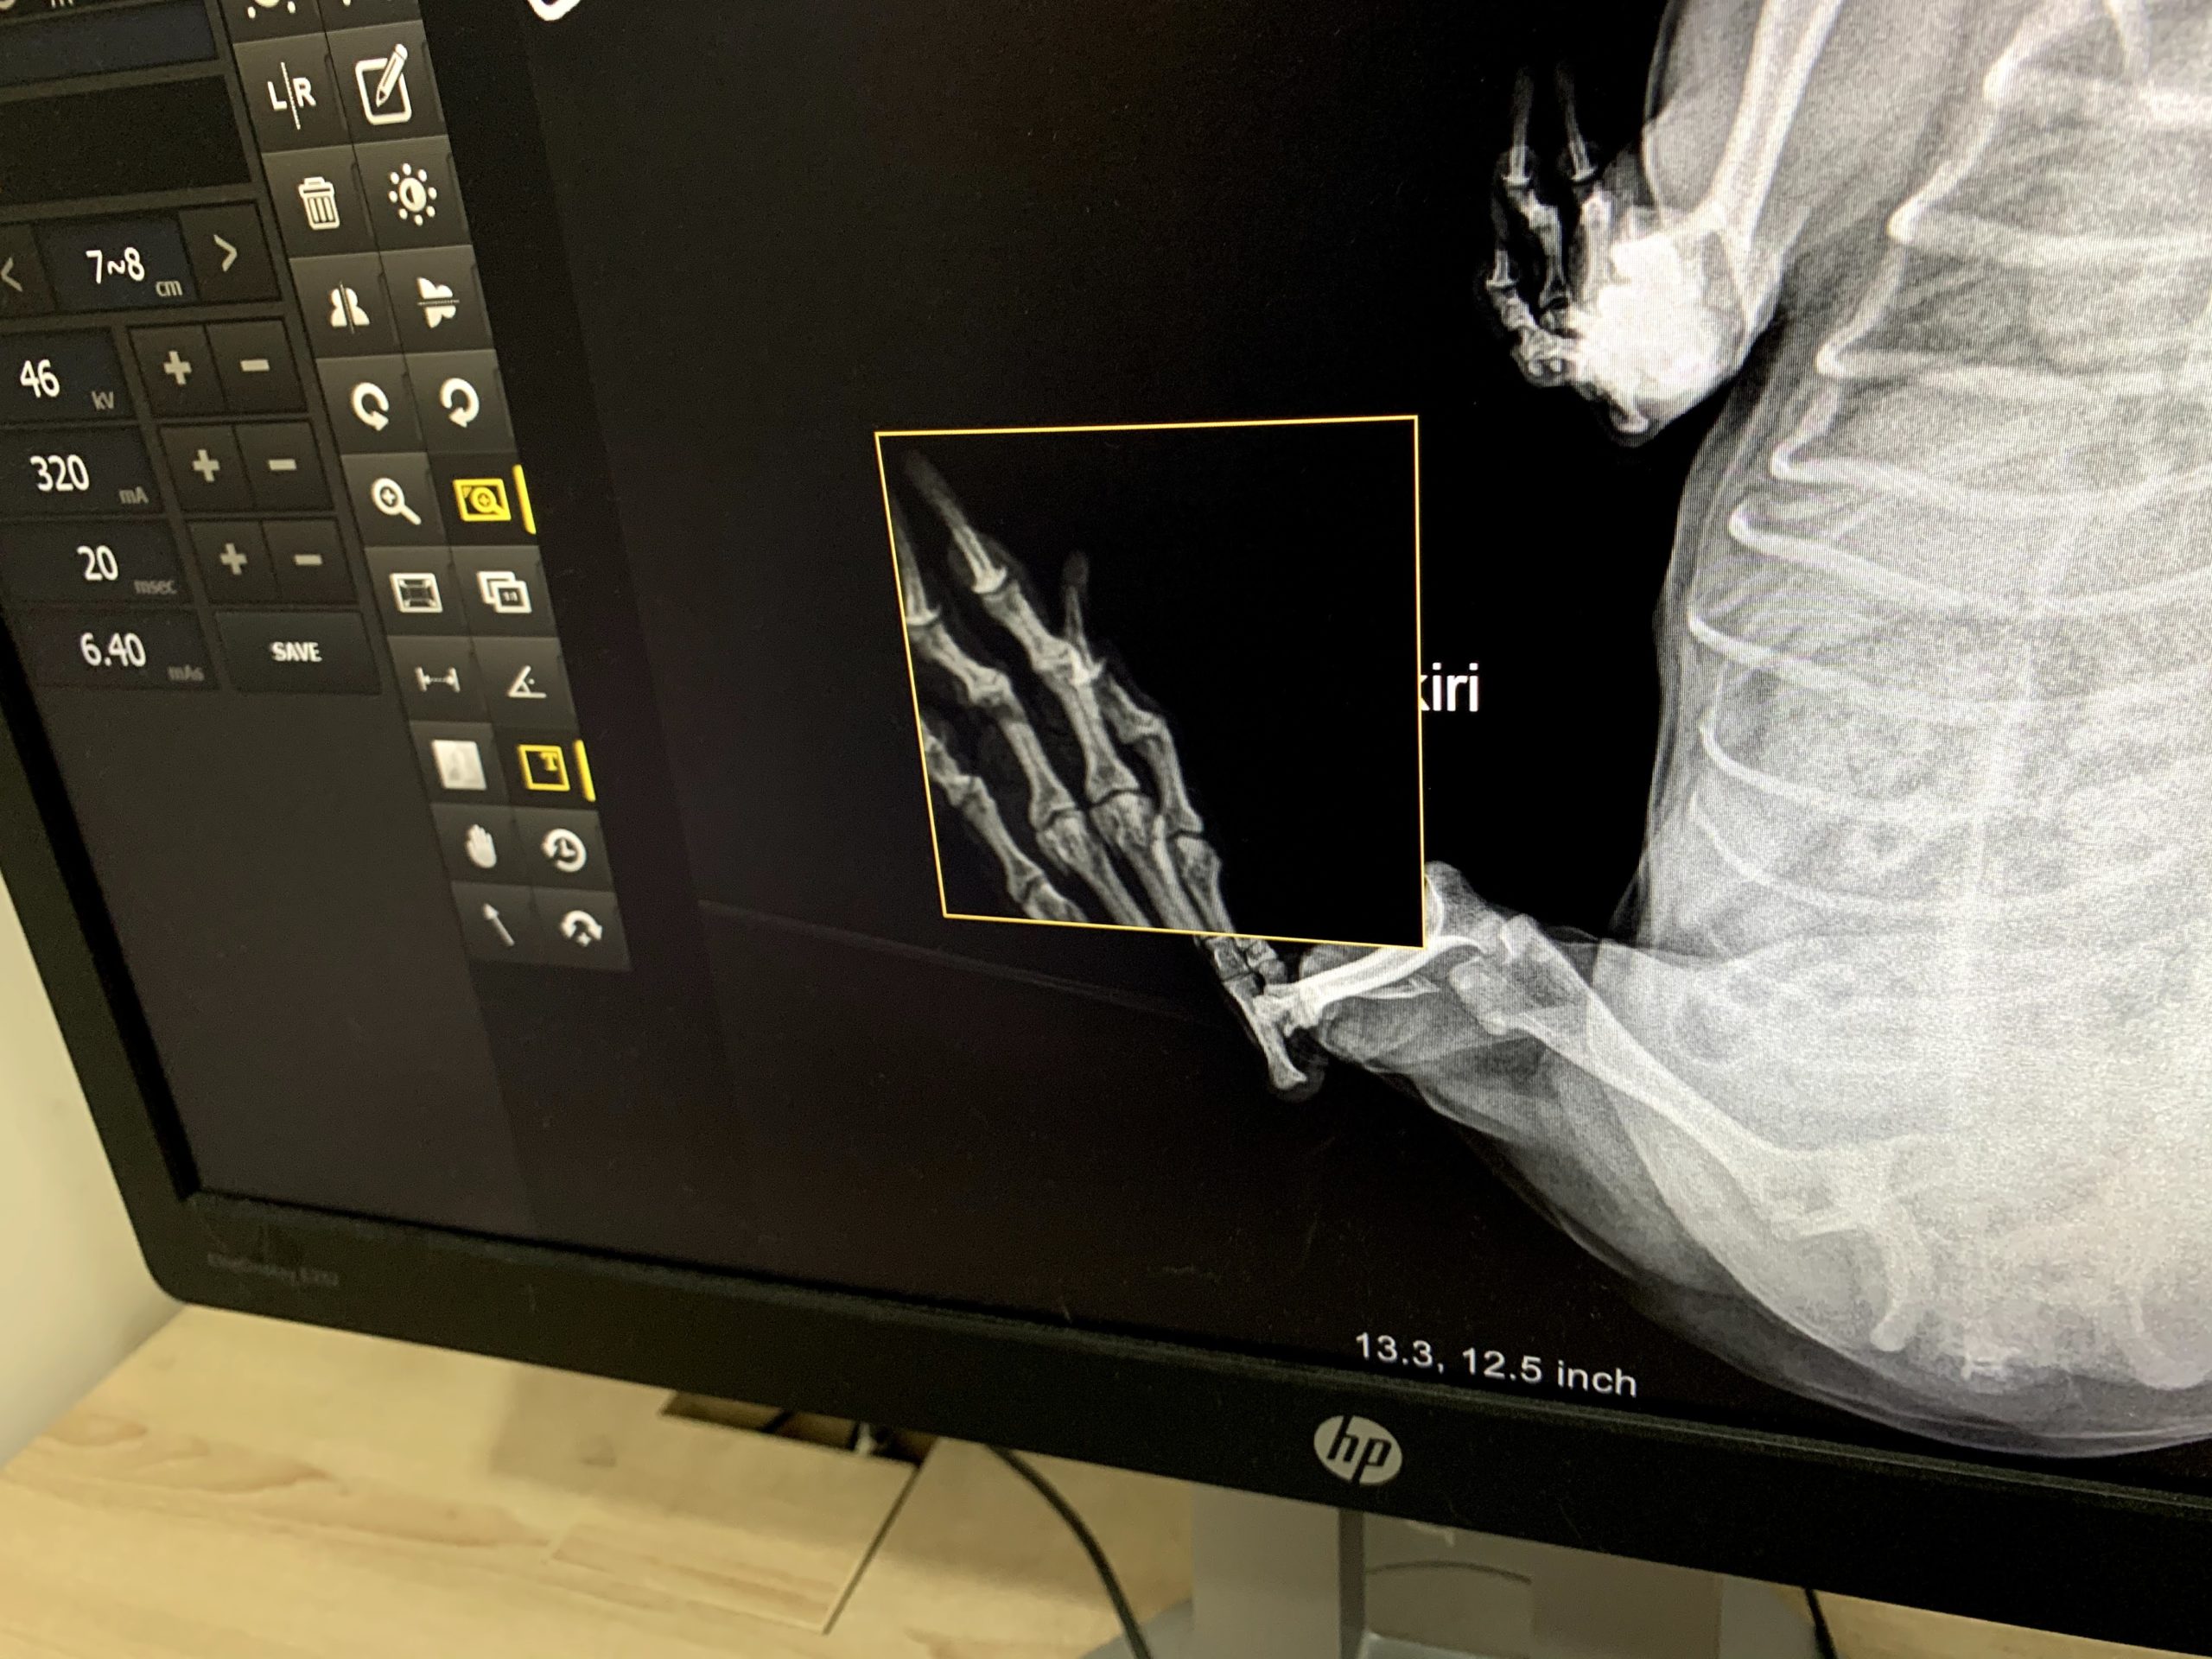

さて、今回ご紹介したいのは、インドネシアの獣医師についてです。 学位取得で国家試験がないインドネシアの獣医師のレベルはピンキリです。愛犬が病気・ケガをした際、○○動物病院の○○先生、の先生の名前をいい、その先生に診察してもらってください。もし、日本でかかりつけの獣医師がいましたら、電話で相談できる体制を準備した方がよいかと思います。

誤診は日常茶飯事ですし、まだ一部のインドネシア人ペットは動物であって、一家族として考えていません。